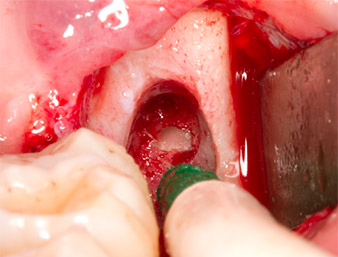

Per ottenere materiale autogeno per il successivo trattamento della ferita, sono stati estratti frammenti di osso sano nella zona del residuo di radice con uno strumento piezochirurgico (Piezomed B5) (Fig. 5).

Piezomed B5

Fig. 5: L'osso nella regione dell'alveolo è sollevato con uno strumento piezochirurgico a forma di scalpello (Piezomed B5). Tale osso è utilizzato come materiale autologo di rinforzo dopo la rimozione del residuo di radice (vedere Fig. 13 e 14).

Il tessuto autogeno è stato rimosso con la sezione a forma di raschietto della parte funzionante dello strumento e conservato un una soluzione salina fisiologica per uso successivo (vedere Fig. 13).